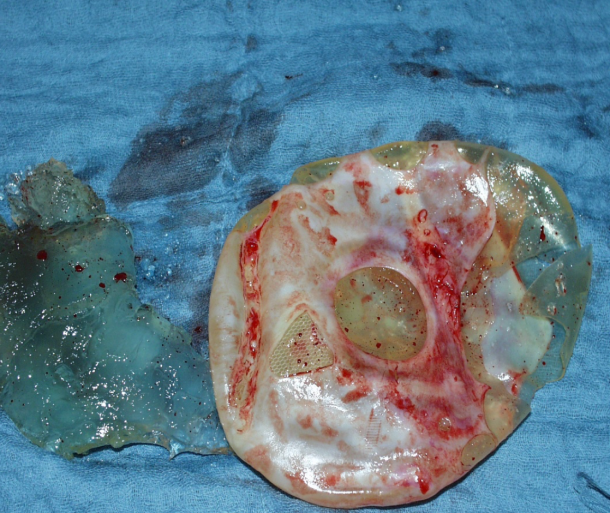

Other possible complications of gluteal implants

explosion gluteal implant